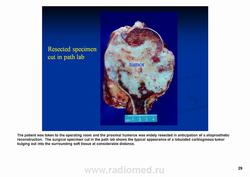

Клиническая картина. Периферические опухоли медленно увеличиваясь, не вызывая боли, достигают больших размеров; центральные опухоли — прогрессивно усиливающиеся боли.

Рентгенологически выявляют в очаге деструкции участки обызвествления в виде крапчатости; кортикальный слой с признаками эрозии со стороны эндоста и истончения; размеры опухоли более 4 см; периостальная реакция слабо выражена или отсутствует; может наблюдаться деструкция кортикальной кости и наличие мягкотканного компонента; в длинных костях локализуется чаще в метафизах и диафизах; интенсивное внутрикостномозговое распространение.